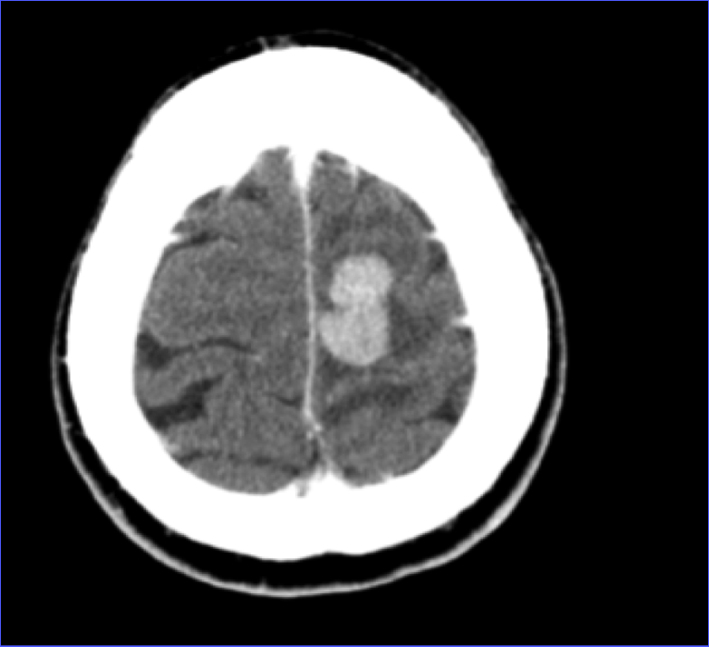

CT of head showed a left frontal 2.6 × 1.5 cm mass (Fig. 1, 2). MRI of brain done showed a 2.7 × 1.9 × 1.7 cm lobulated oval shaped mass located in left parafalcine posterior frontal area with perilesional edema with mass effect on precentral gyrus and effacement of central sulcus.

![]() Click for large image | Figure 1. CT of head axial view showing left frontal mass. |